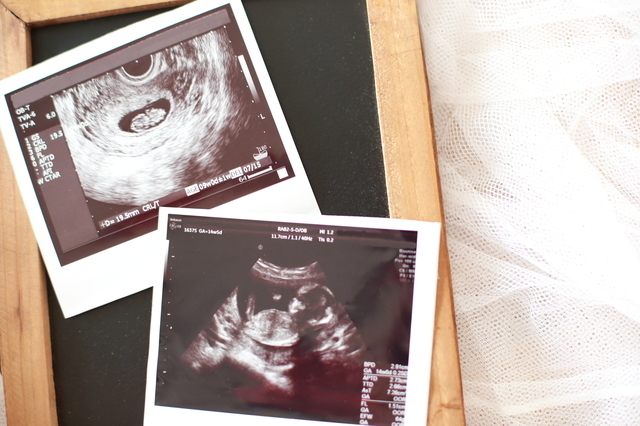

赤ちゃんの心拍確認がとれ、超音波(エコー)検査では頭、胴、足がはっきりと分かれて手が見える姿も確認することができ、赤ちゃんの成長を実感するママも多いです。